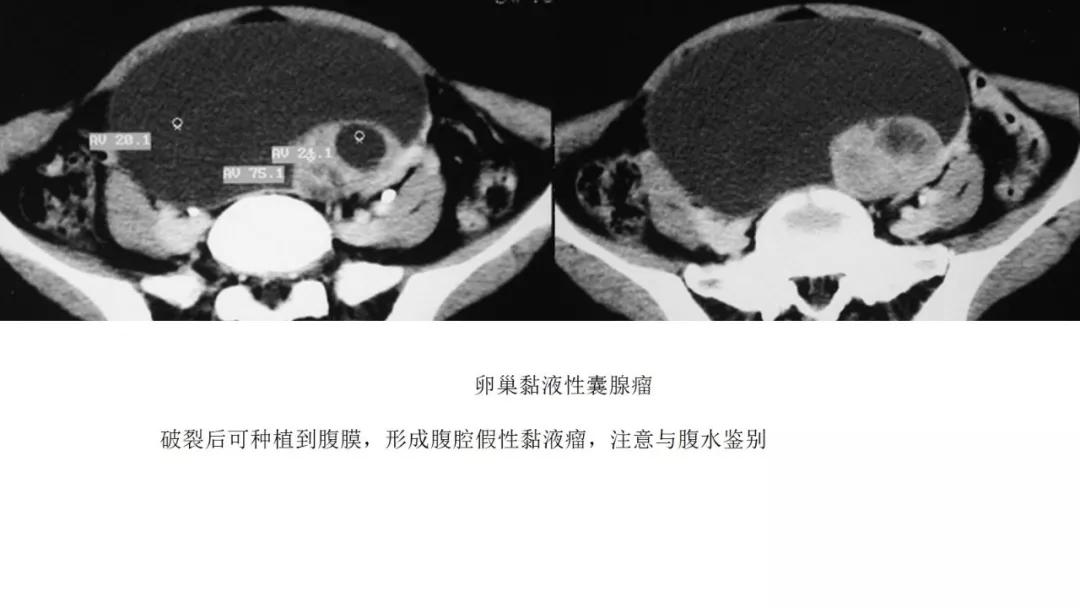

- 卵巢的黏液性肿瘤破裂,上皮和黏液会种植在腹膜引起胶冻样的腹膜假黏液瘤,这一点跟阑尾的黏液性肿瘤类似,都是腹膜假黏液瘤的病因。